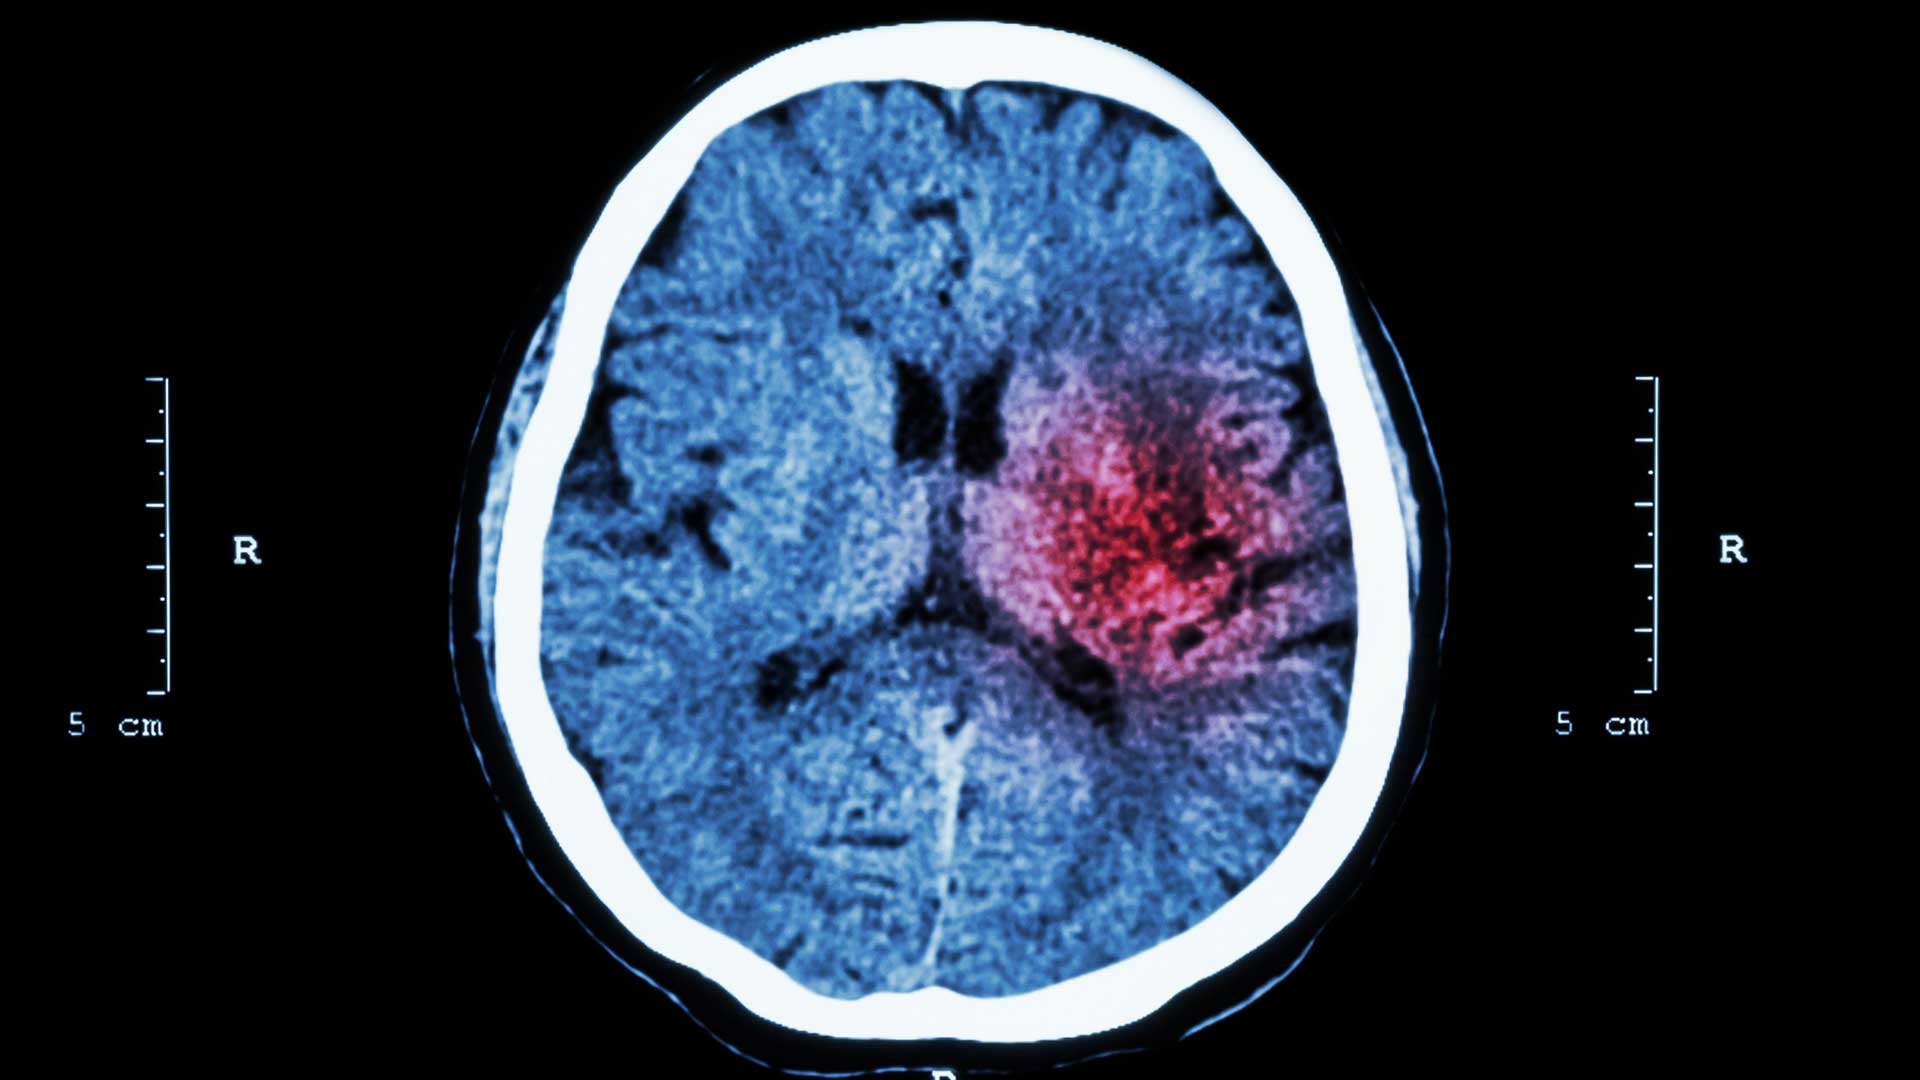

Hjerneslag er en fellesbetegnelse for hjerneinfarkt og hjerneblødning.

Hjerneslag skyldes enten blodpropp i hjernen eller en blødning i hjernens blodårer. Avhengig av området som rammes, kan hjerneslag gi lammelser, talevansker, synsforstyrrelser og bevisstløshet.

Hjerneblødning

Hjerneblødning kan oppstå i alle deler av hjernen, eller på hjernens overflate, og omfatter mellom 10-15 prosent av alle hjerneslag.